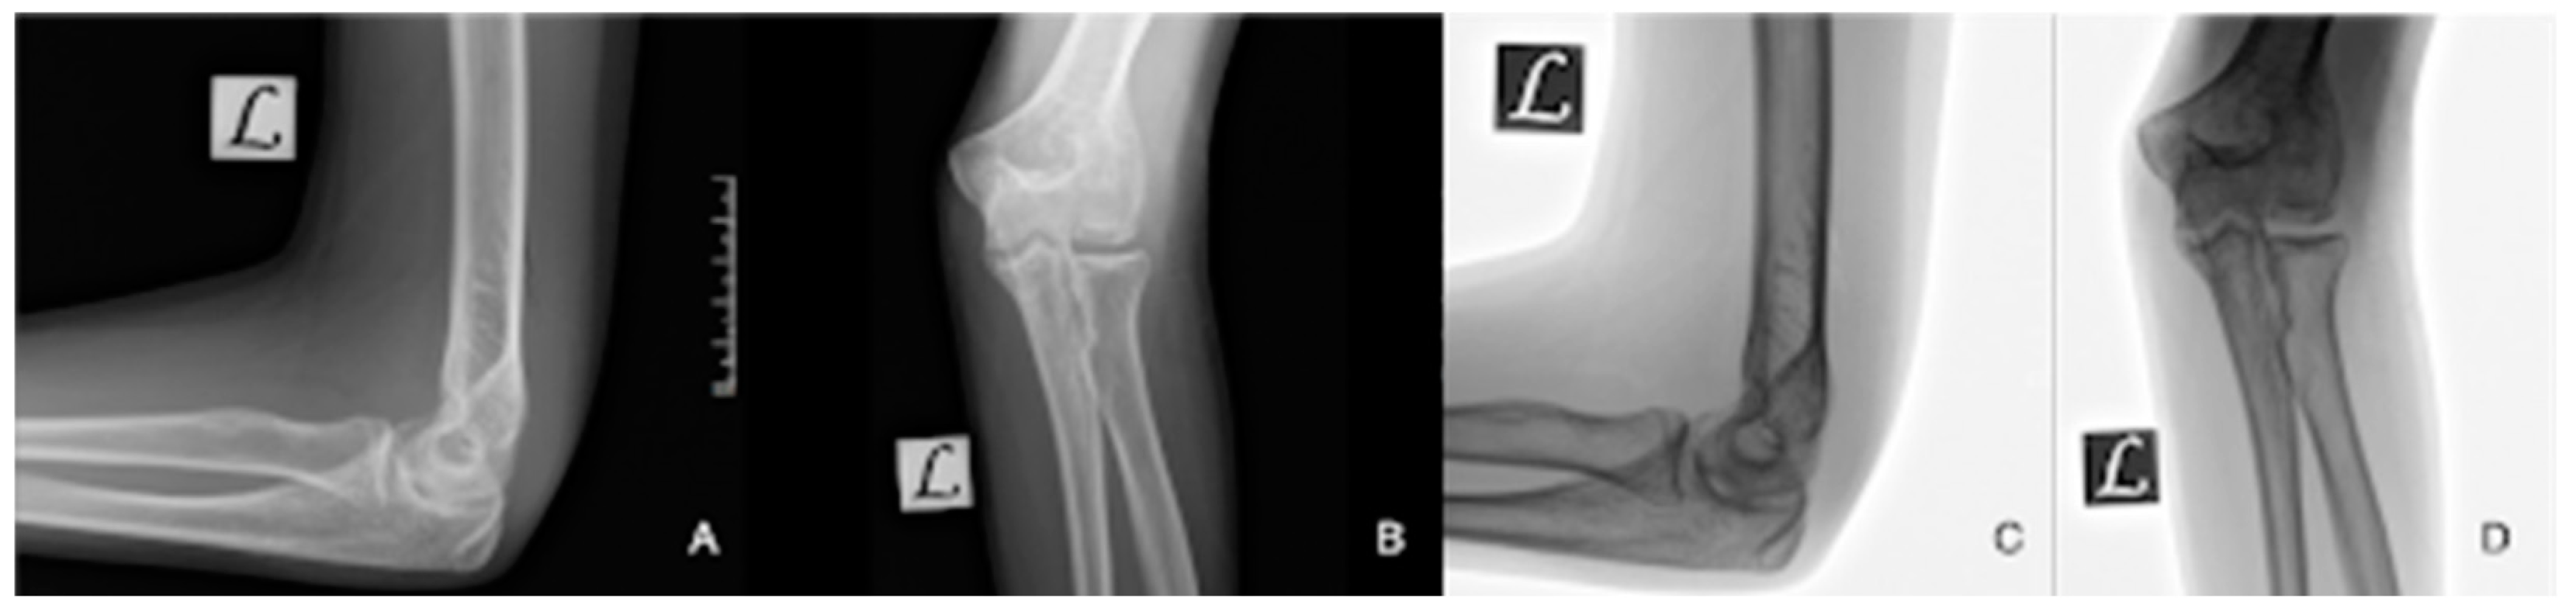

| Imaging: | X-ray | Arthroscopy | MRI | |||

|---|---|---|---|---|---|---|

| Classification | Berndt and Harty [21]—1959 | Guhl [22]—1982 | ICRS by Brittberg and Winalsky [23]—2003 | DiPaola [24]—1991 | Hefti [4]—1999 | Ellerman [15]—2019 |

| Stage 1 | Small subchondral compression | Intact Lesion | A stable lesion of the softened area covered by intact cartilage | Thickening of articular cartilage and low signal changes | Small change in signal, without clear fragment margins | Epiphyseal cartilage lesion with necrotic center |

| Stage 2 | Partially detached osteochondral fragment | A lesion with signs of early separation | Lesions with partial discontinuity which are stable when probed | Articular cartilage is breached, with a low signal rim behind the fragment indicating fibrous attachment | Osteochondral fragment with clear margins, without fluid in between | Epiphyseal cartilage lesion with complete or incomplete rim calcification |

| Stage 3 | Completely detached, non-displaced | Partially detached lesion | Lesions with complete discontinuity which are not dislocated (Dead in situ) | High signal changes behind the fragment indicate synovial fluid between the fragment and the underlying subchondral bone | Fluid is partially visible between the fragment and bone | Partially or completely ossified lesion |

| Stage 4 | Completely detached and displaced—loose body | Craters with loose bodies (salvageable or non-salvageable) | Empty defect bed with loose or dislocated fragment | Loose body | Fluid surrounds the fragment but it is still in situ | Healed osseous lesion with scar |

| Stage 5 | Scranton and McDermott modification: Subchondral Cyst | - | - | - | The fragment is completely detached and displaced | Unhealed, detached osseous lesion (Sequestrum) |